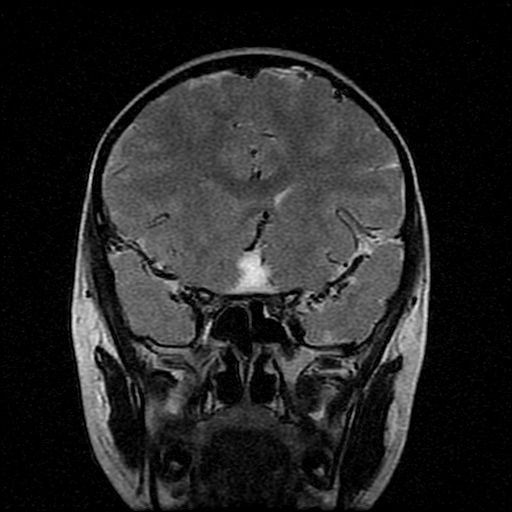

男性,12岁。反复头痛呕吐半月。脑积液无异常。病变部位ct值32hu,dwi无异常。

鞍上为主,累及鞍内,垂体受压位于鞍底。mri呈短t1、长t2信号,不太支持生殖细胞肿瘤,首考颅咽管瘤。

鞍内囊性占位性病变,t1wi、t2wi,均为高信号影。ct平扫为等密度。发病年龄较小。故首先考虑颅咽管瘤,可以做ct增强扫描